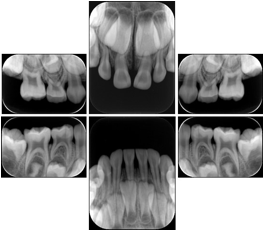

Intra-oral radiography typically involves acquisition of multiple images of various parts of the dentition. Many digital radiographic systems offer customized templates that are used for displaying the images in a study on the screen. These templates may also be referred to as mounts or view sets. The Structured Display Object represents a standard method of encoding and exchanging the layout and intended display of Structured Displays. A structured display object created in this manner could be stored with a study and exchanged with images to allow for complete reproduction of the original exam.

3. A dental provider wishes to capture a series of DICOM IO images for the patient’s dentition. The tooth morphology, teeth are divided into molars, premolars, canines and incisors, and a number of images for each jaw. The anatomic information was captured utilizing the triplet of schema. This standard code sequence is based on ISO 3950-2010, Dentistry - Designation system for teeth and areas of the oral cavity.

Every IO image should have anatomic information either through the primary or modifier sequence.

In most standard cases, images are oriented in structured layouts. These structured displays are useful to be shared between providers for reference purposes.

Table OO.1.1-1 shows structured display standard templates, where Viewset ID is based on the Japanese Society for Oral and Maxillofacial Radiology (JSOMR) classification provided by JIRA (Japan Medical Imaging and Radiological Systems Industries Association, www.jira-net.or.jp). Expected or typical teeth to be imaged location, region and designation codes are based on ISO 3950-2010, Dentistry - Designation system for teeth and areas of the oral cavity. For all the hanging protocols listed in OO.1.1-1, the value to use for Hanging Protocol Creator (0072,0008) is "JSOMR" and the value to use for Hanging Protocol Name (0072,0002) does not include "JSOMR" (e.g., "DL-S001A", not "JSOMR DL-S001A").